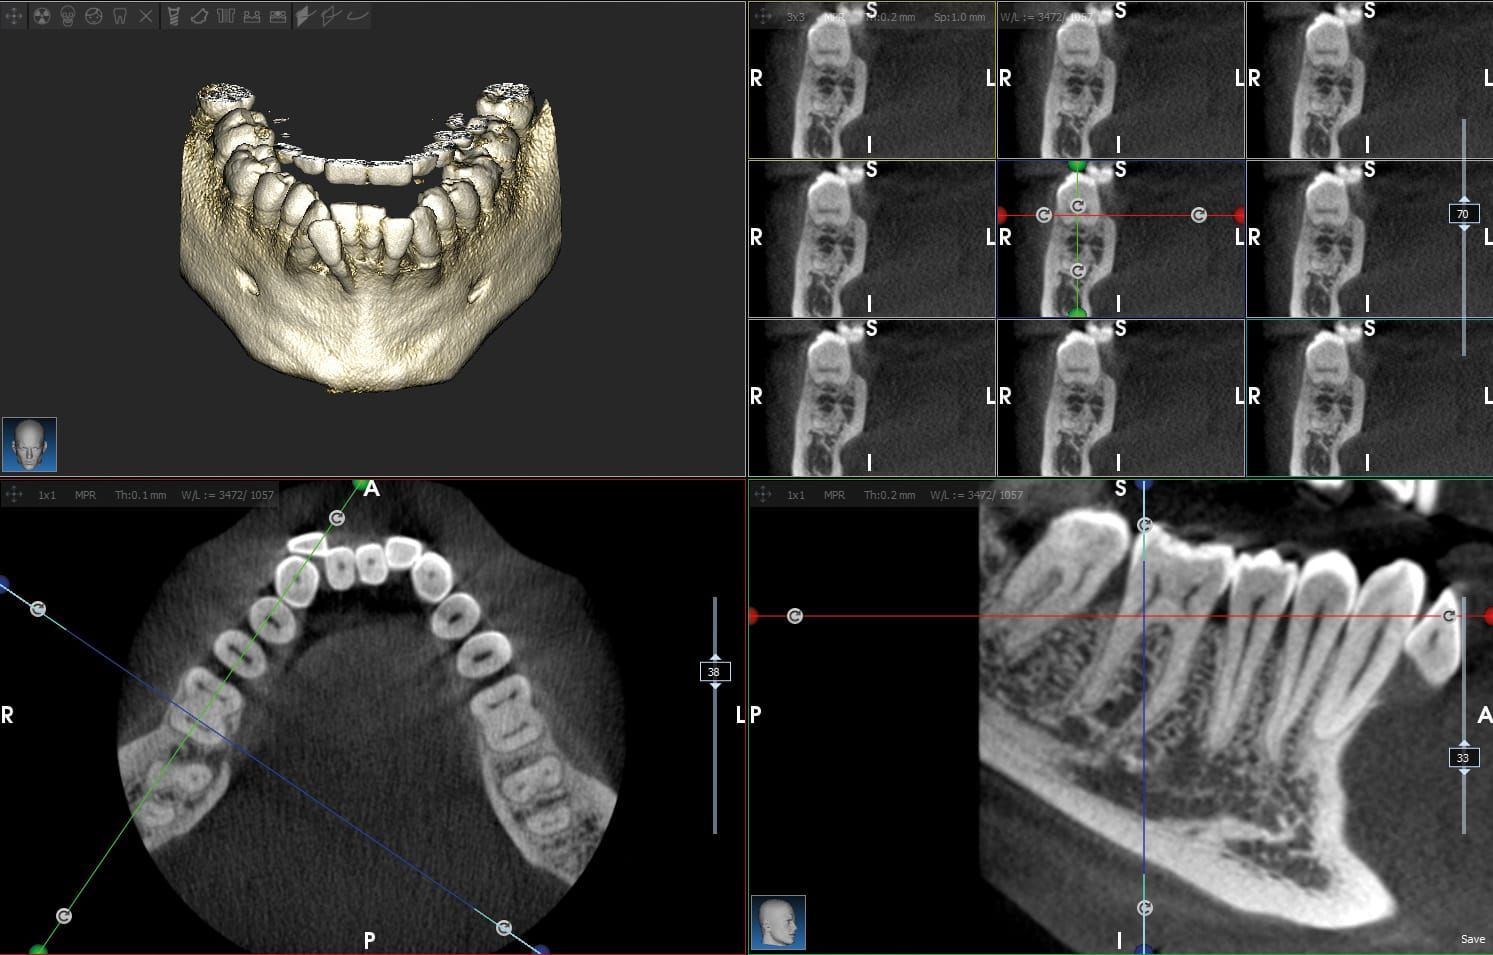

Il nostro studio è dotato di una reception, una sala d'attesa, un ufficio, 3 sale operative di cui una dotata di MICROSCOPIO OPERATORIO, una sala sterilizzazione, un magazzino, una rete di computer che serve ogni locale, una centralizzazione del condizionamento ambientale e un locale radiografico per Tac 3D e panoramiche digitali.

Per tutelare al massimo i nostri pazienti utilizziamo apparecchiature radiografiche digitali, che permettono di erogare una quantità minima di raggi X con risultati ottimali.